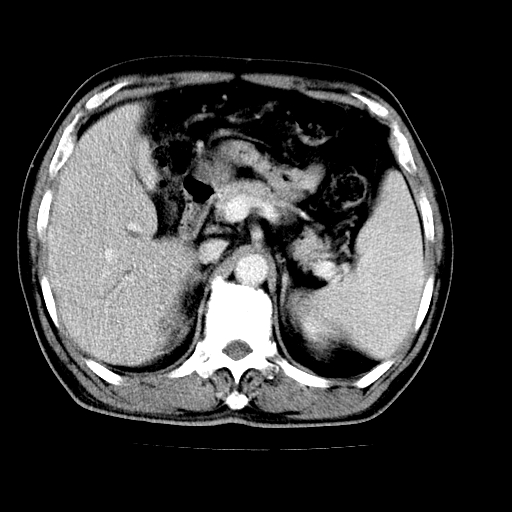

男,66岁,上腹部不适、黄染一周。彩超示:肝左叶占位,肝内胆管扩张,胆总管扩张,胆总管占位?

肝左叶不规则软组织肿块影,边缘不规整邻近肝实质受累分界不清;肝内胆管(左叶)明显扩张成“软藤状”,诊断:肝左叶胆管细胞癌。

肝左叶占位性病变,并胆管扩张,符合胆管细胞癌ct表现,门脉左支受累,左肾囊肿。窗宽太窄了,其他的看不清

左叶胆管细胞癌累及胆总管,门脉左支受侵,慢性胆囊炎胆结石,左肾小囊肿